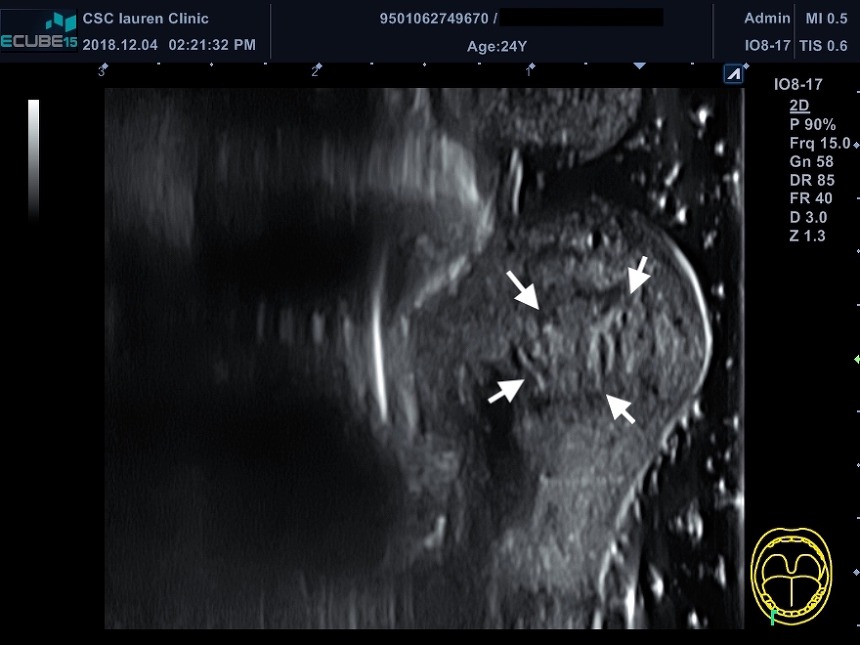

다른 병원에서 입술 필러를 맞은 입술 초음파 사진